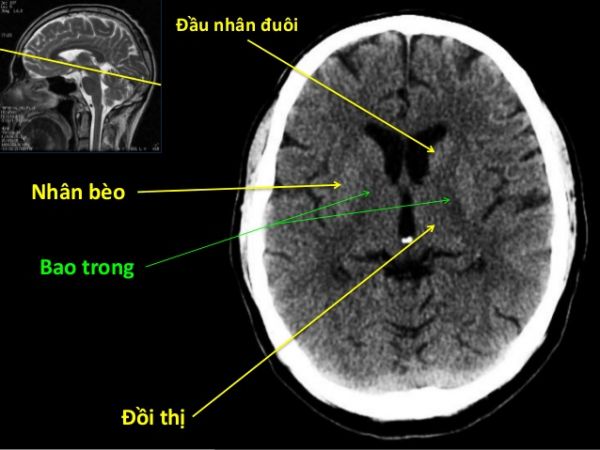

Xuất huyết nhân bèo trái

Trên đây là một số thông tin và hình ảnh về bệnh Xuất huyết nhân bèo trái, hy vọng sẽ giúp các bạn có những kiến thức cơ bản về bệnh để chẩn đoán và điều trị kịp thời!